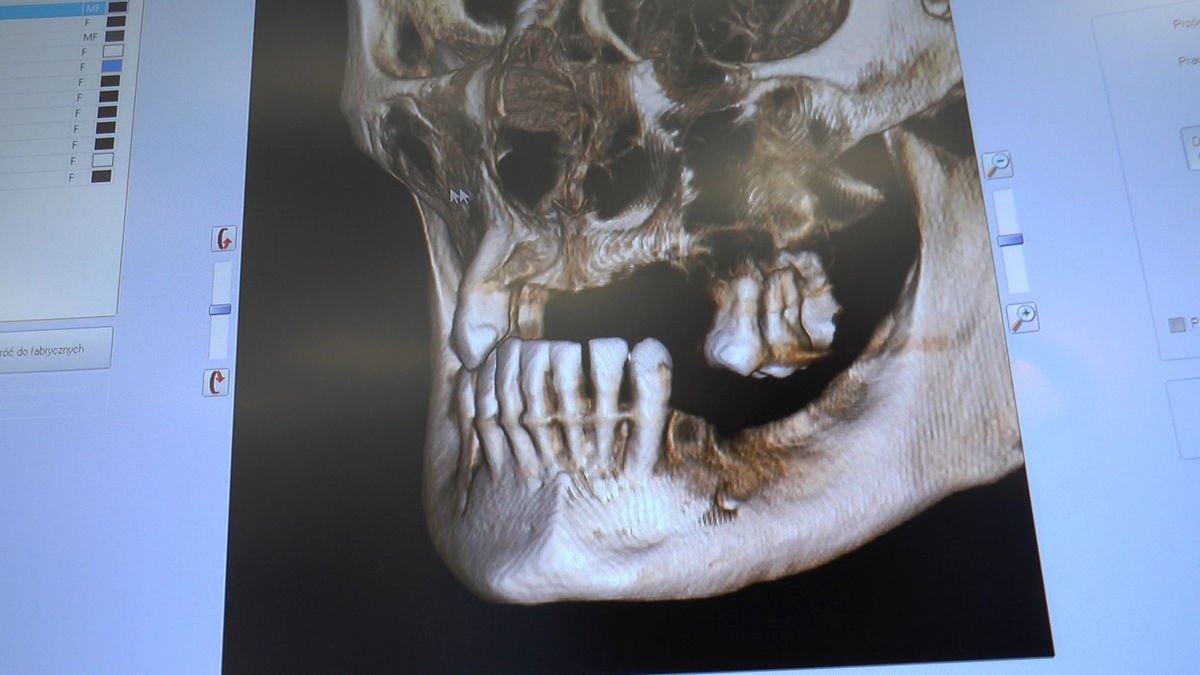

Practiculum Implantologii – Sezon V/B, sesja 8, część 4